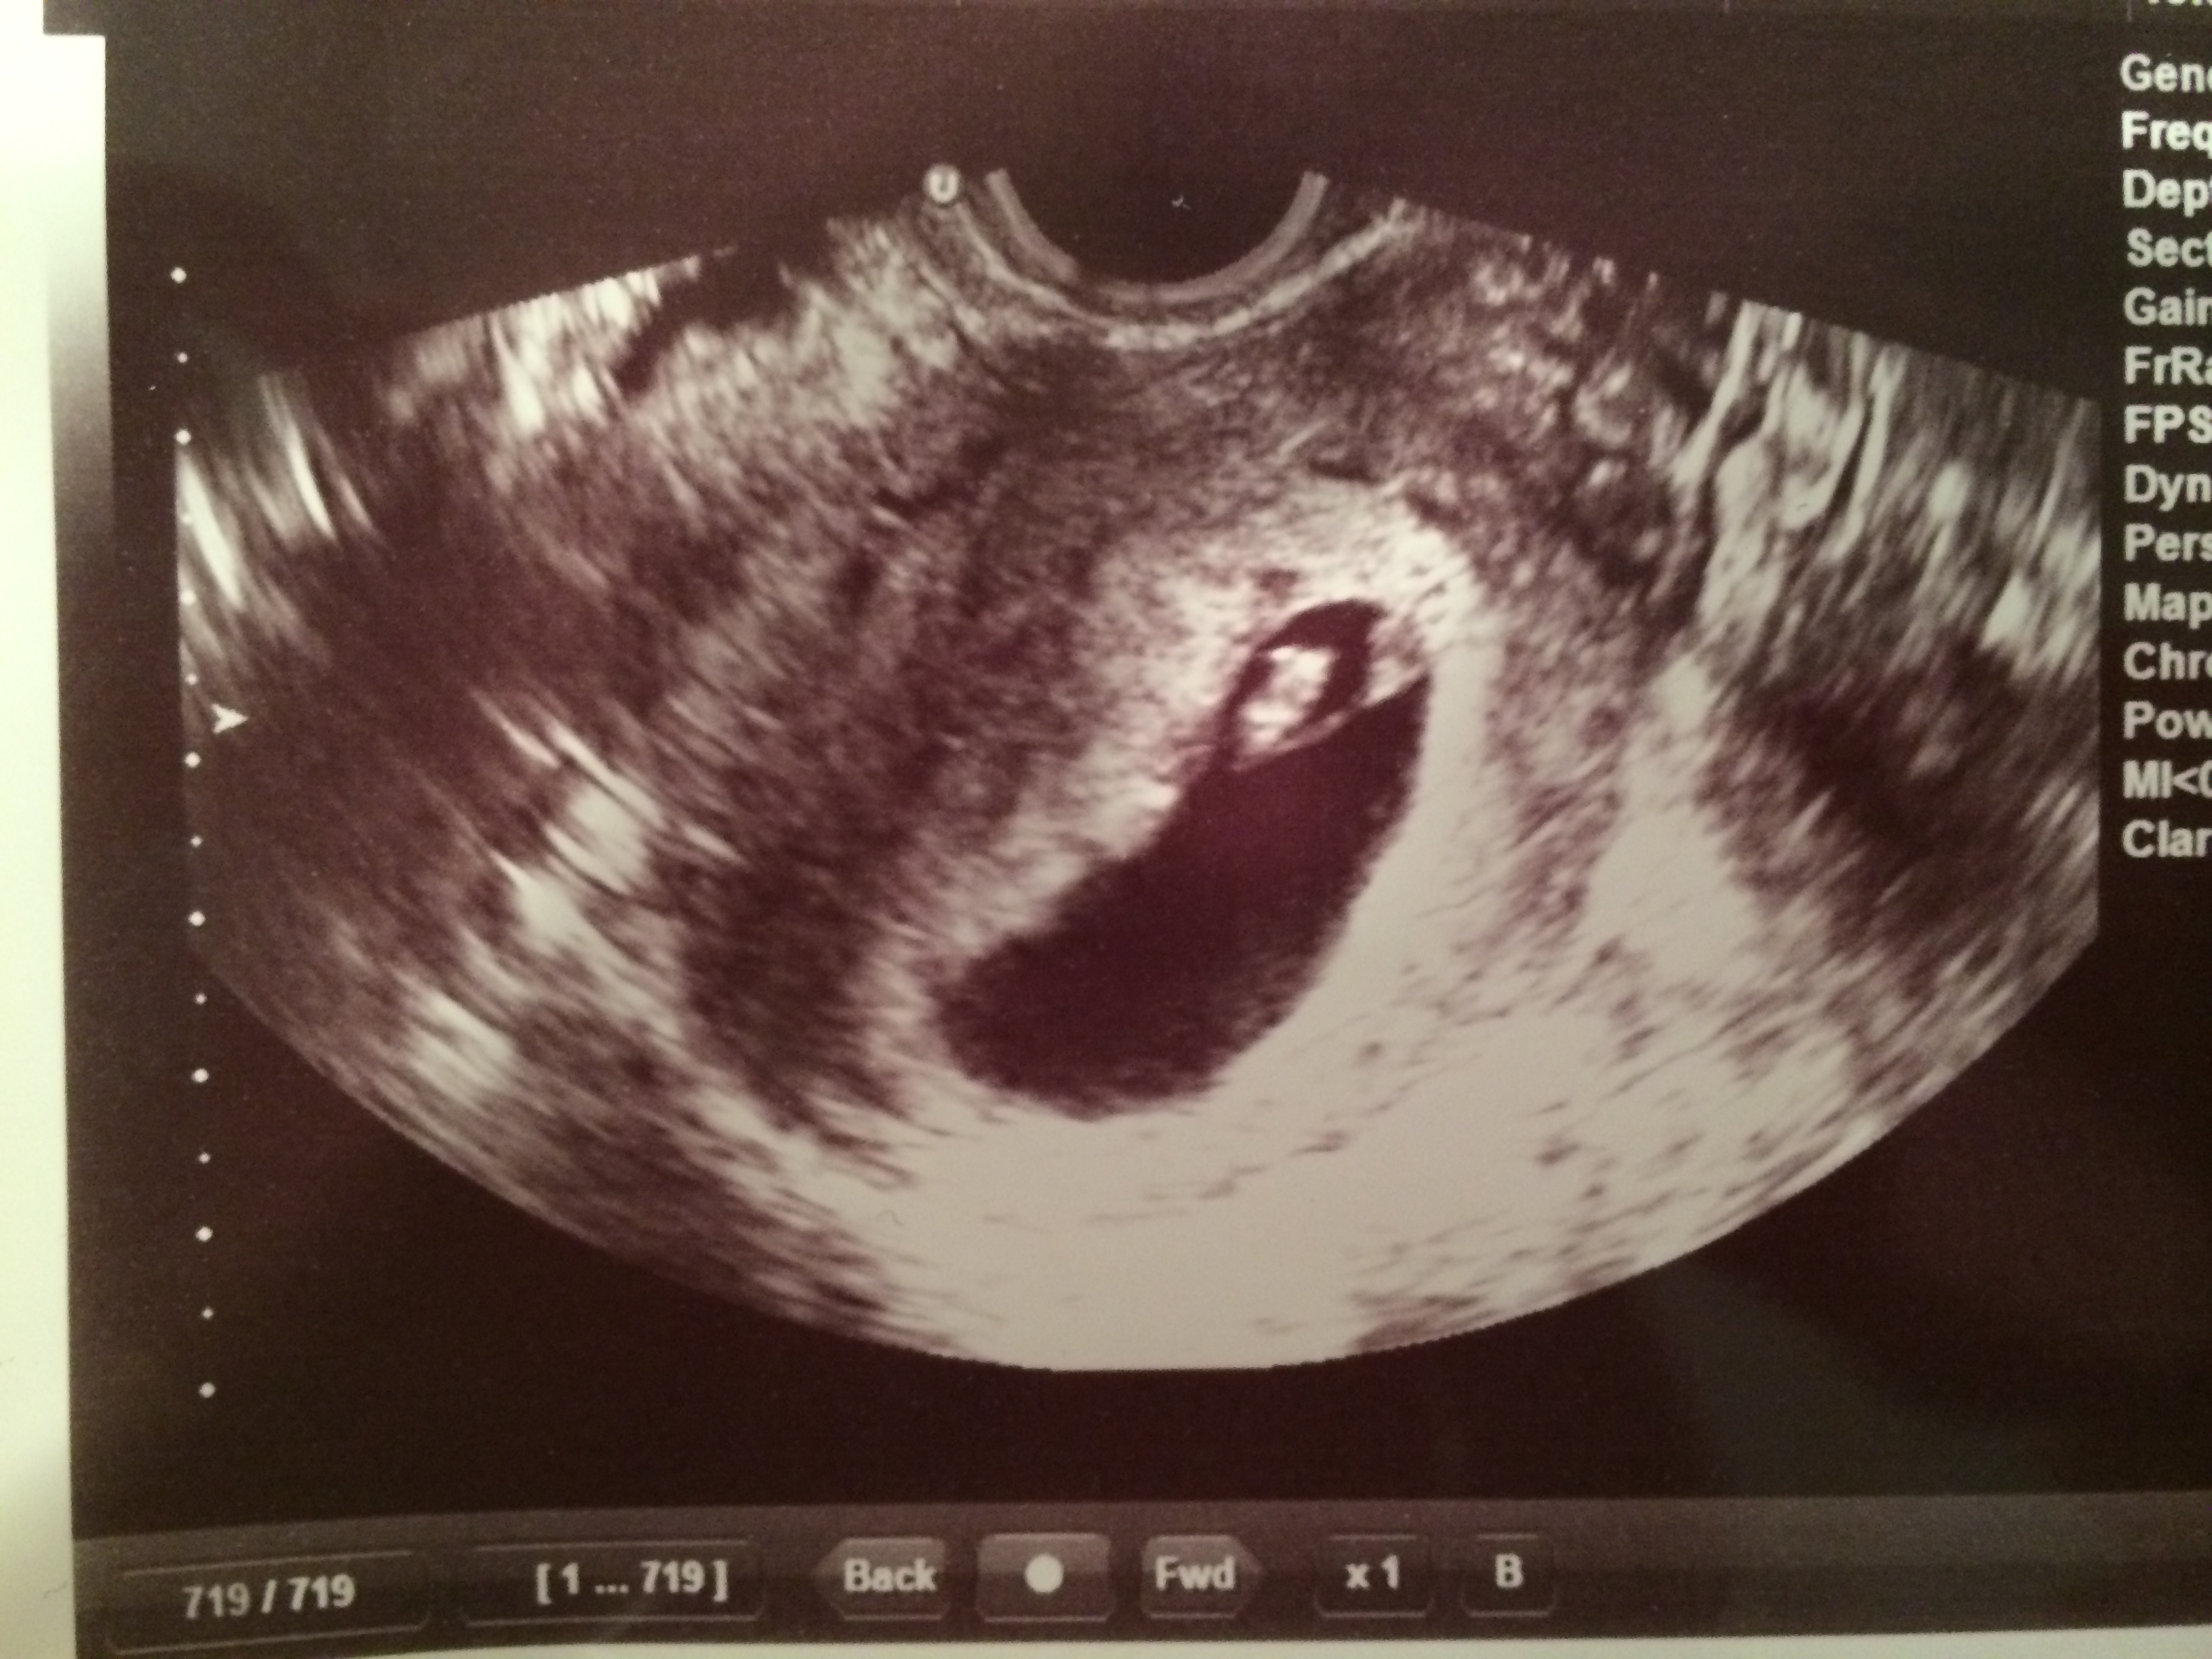

I posted a pic last week at 6 weeks where baby and yolk sac were in the middle at the top. Today, I went in at 7 weeks 1 day for transvaginal and everything seemed a bit more clear. I can't seem to think this would be anything but a boy, but thought I would throw it out there in case I was missing something. Baby on the left attached to yolk sac on the right. Seems like the cookie cutter boy pic, doesn't it?!?! Grasping for straws here..... Thanks!Attachment 15661

Sorry I can't help much as I find Ramzi so confusing. As far I know, being a transvag there's no flipping required (still breaking my head over that), so yes, it does look all boy following the theory. Hope that's what you want.